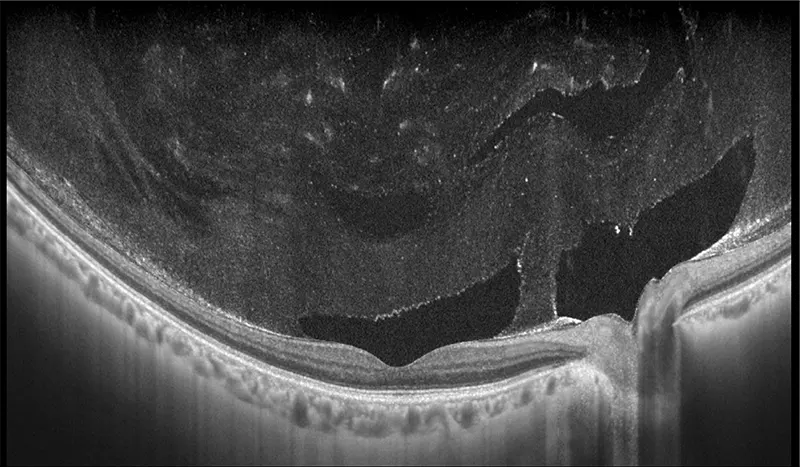

Galería OCTs del TowardPi Yalkaid